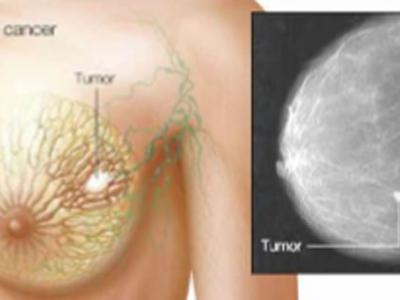

《临床研究杂志》:用于治疗血癌的药物可

《临床研究杂志》:用于治疗血癌的药物可能对治疗三阴性乳腺癌...